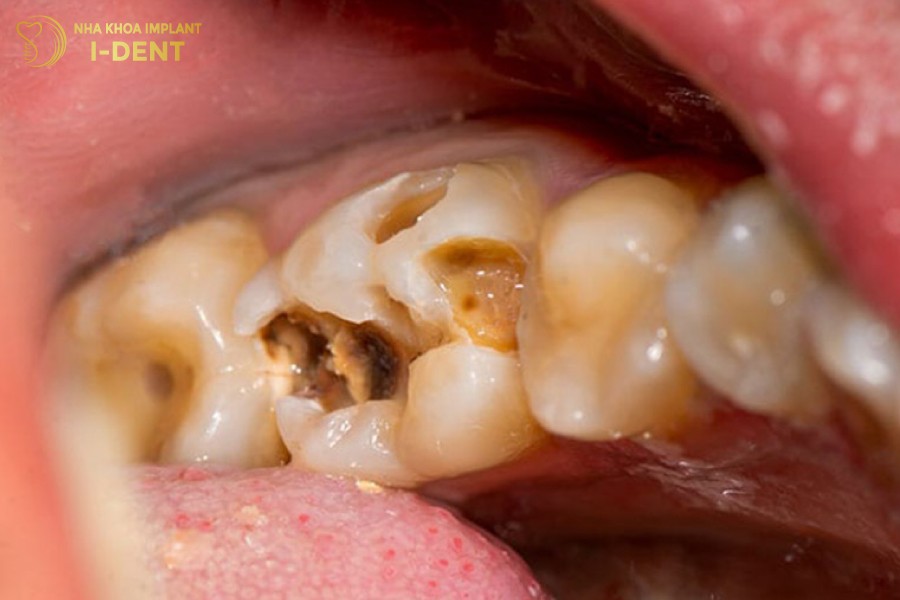

Khi sức khỏe răng miệng tốt, tủy răng được bảo vệ bởi lớp men và ngà răng, không bị tấn công bởi vi khuẩn có hại. Tuy nhiên, khi răng bị nứt vỡ hoặc sâu răng, vi khuẩn sẽ thông qua đó để xâm nhập gây viêm tủy răng.

Viêm tủy răng có thể diễn biến qua nhiều giai đoạn và nhiều dạng tổn thương khác nhau, bao gồm:

- Hoại tử tủy là phần tủy bên trong răng đã hoàn toàn chết, tình trạng này còn được gọi là chết tủy răng. Khiến răng không còn cảm giác và dần chuyển sang màu nâu, vàng hoặc đen và răng rất dễ bị gãy rụng.

- Răng bị mẻ, vỡ bởi sâu răng hoặc tai nạn khiến tủy răng bị lộ ra.